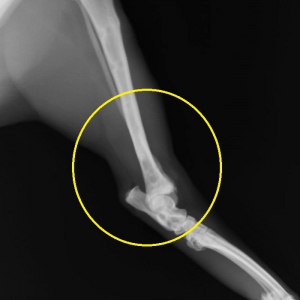

早速ですが、下写真が当院で撮影をやり直した骨折のレントゲン写真です。右写真が「スネの骨」側面から、左が正面像です。「くるぶし」のちょっと上に斜めに大きくずれた骨折が見られます。(黄色丸の中)

骨折は脛骨(スネの骨)の骨折とそのお隣の細い骨、腓骨の(骨が外に出ていない)単純骨折です。通常、腓骨は脛骨とともに折れますから、以下、まとめて脛骨骨折とします。

骨折の分類としては骨に対して斜めに骨折線が走る、斜骨折と言います。また、骨折部位が骨の端にあるため、部位的には「遠位端骨折」といいます。遠位端の斜骨折は整復の難しい骨折のひとつです。